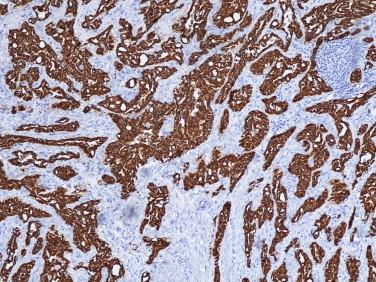

O estudo histológico revelou uma neoplasia formada por células epitelioides ou endotelioides dispostas em túbulos, cordões ou pequenos ninhos, de núcleo regular com pequeno nucléolo e citoplasma eosinófilo ou vacuolizado, conferindo por vezes uma morfologia tipo anel de sinete; estavam envolvidas por um estroma fibroso com discreto infiltrado linfocítico (fig. 1 ). A caracterização imuno‐histoquímica demonstrou positividade intensa e difusa para AE1/AE3 e calrretinina (Figura 2  ;  Figura 3 ), com negatividade para Ber‐Ep4. O diagnóstico histopatológico final foi de tumor adenomatoide paratesticular direito.

Tumor adenomatoide paratesticular – marcação imuno‐histoquímica positiva para ...

Figura 2.

Tumor adenomatoide paratesticular – marcação imuno‐histoquímica positiva para pancitoqueratina AE1/AE3 (100 x).